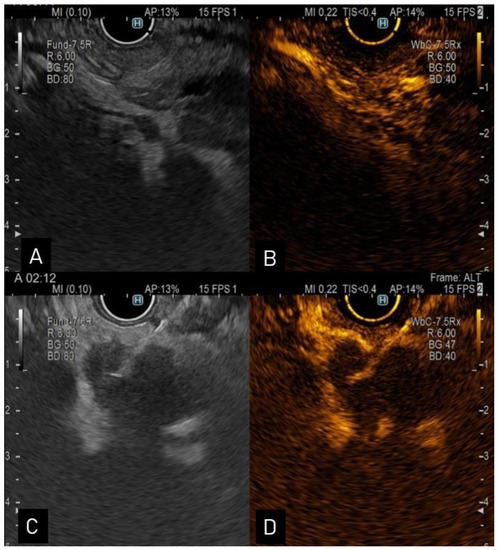

The EUS aspect suggestive of CCA is a mass extending beyond the bile duct wall or periductal infiltration, with a wall thickness of more than 3 mm, or an intraductal mass-growing lesion [34,35] (Figure 1). In previous research, distal tumors which were closer to the EUS transducer were diagnosed in 100% of the cases, while tumors located further from the transducers were only diagnosed in 83% of the cases. Overall, EUS performed better in identifying tumors in comparison to CT or MRI (94, 30, 42%) [36]. Extrahepatic CCAs were diagnosed at an early stage when MRCP was followed by EUS (sensitivity 90% and specificity 98%) [37]. EUS is also useful when assessing common bile duct dilatation associated with normal hepatic tests and inconclusive imaging [38].

Figure 1.

(A). Endoscopic ultrasound view of a distal CCA; (B). contrast enhanced-ultrasound showing hyperenhancement in the arterial phase; (C). endoscopic ultrasound view of a proximal hypoechoic bile duct lesion undergoing aspiration via a 22-G needle; (D). contrast enhanced-ultrasound guided aspiration.